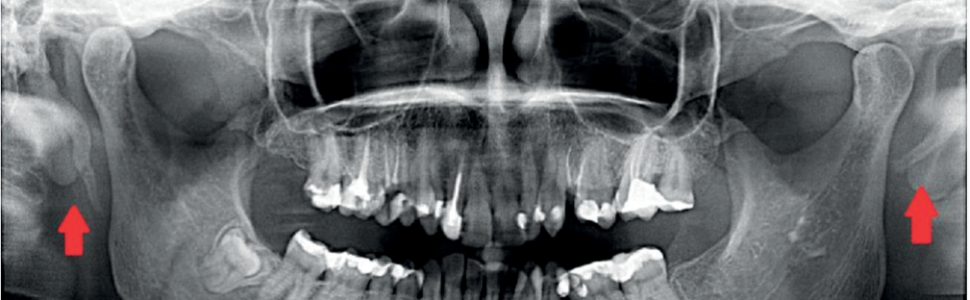

Zespół wydłużonego wyrostka rylcowatego – zespół Eagle'a

Enlarged styloid process syndrome – Eagle syndrome